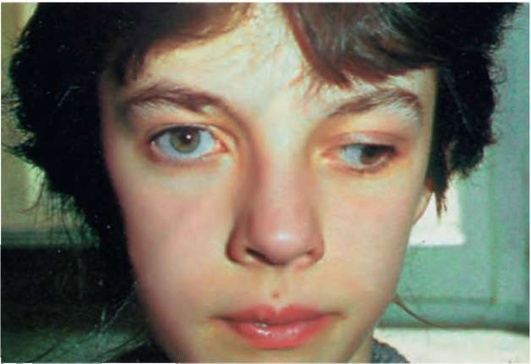

Рис. 5.3. Парез мышц, иннервируемых глазодвигательным (III) нервом. Верхнее веко приспущено, глаз повернут кнаружи, возможна анизокория

Рис. 5.5. Поражение правого VI нерва. При попытке поворота взора вправо проявляется паралич правой прямой мышцы глаза

Рис. 9.2. Симптом Маркуса-Гунна. Пальпебрально-мандибулярная синкинезия: опущенное верхнее веко (птоз) спонтанно поднимается при открывании рта и отведении нижней челюсти